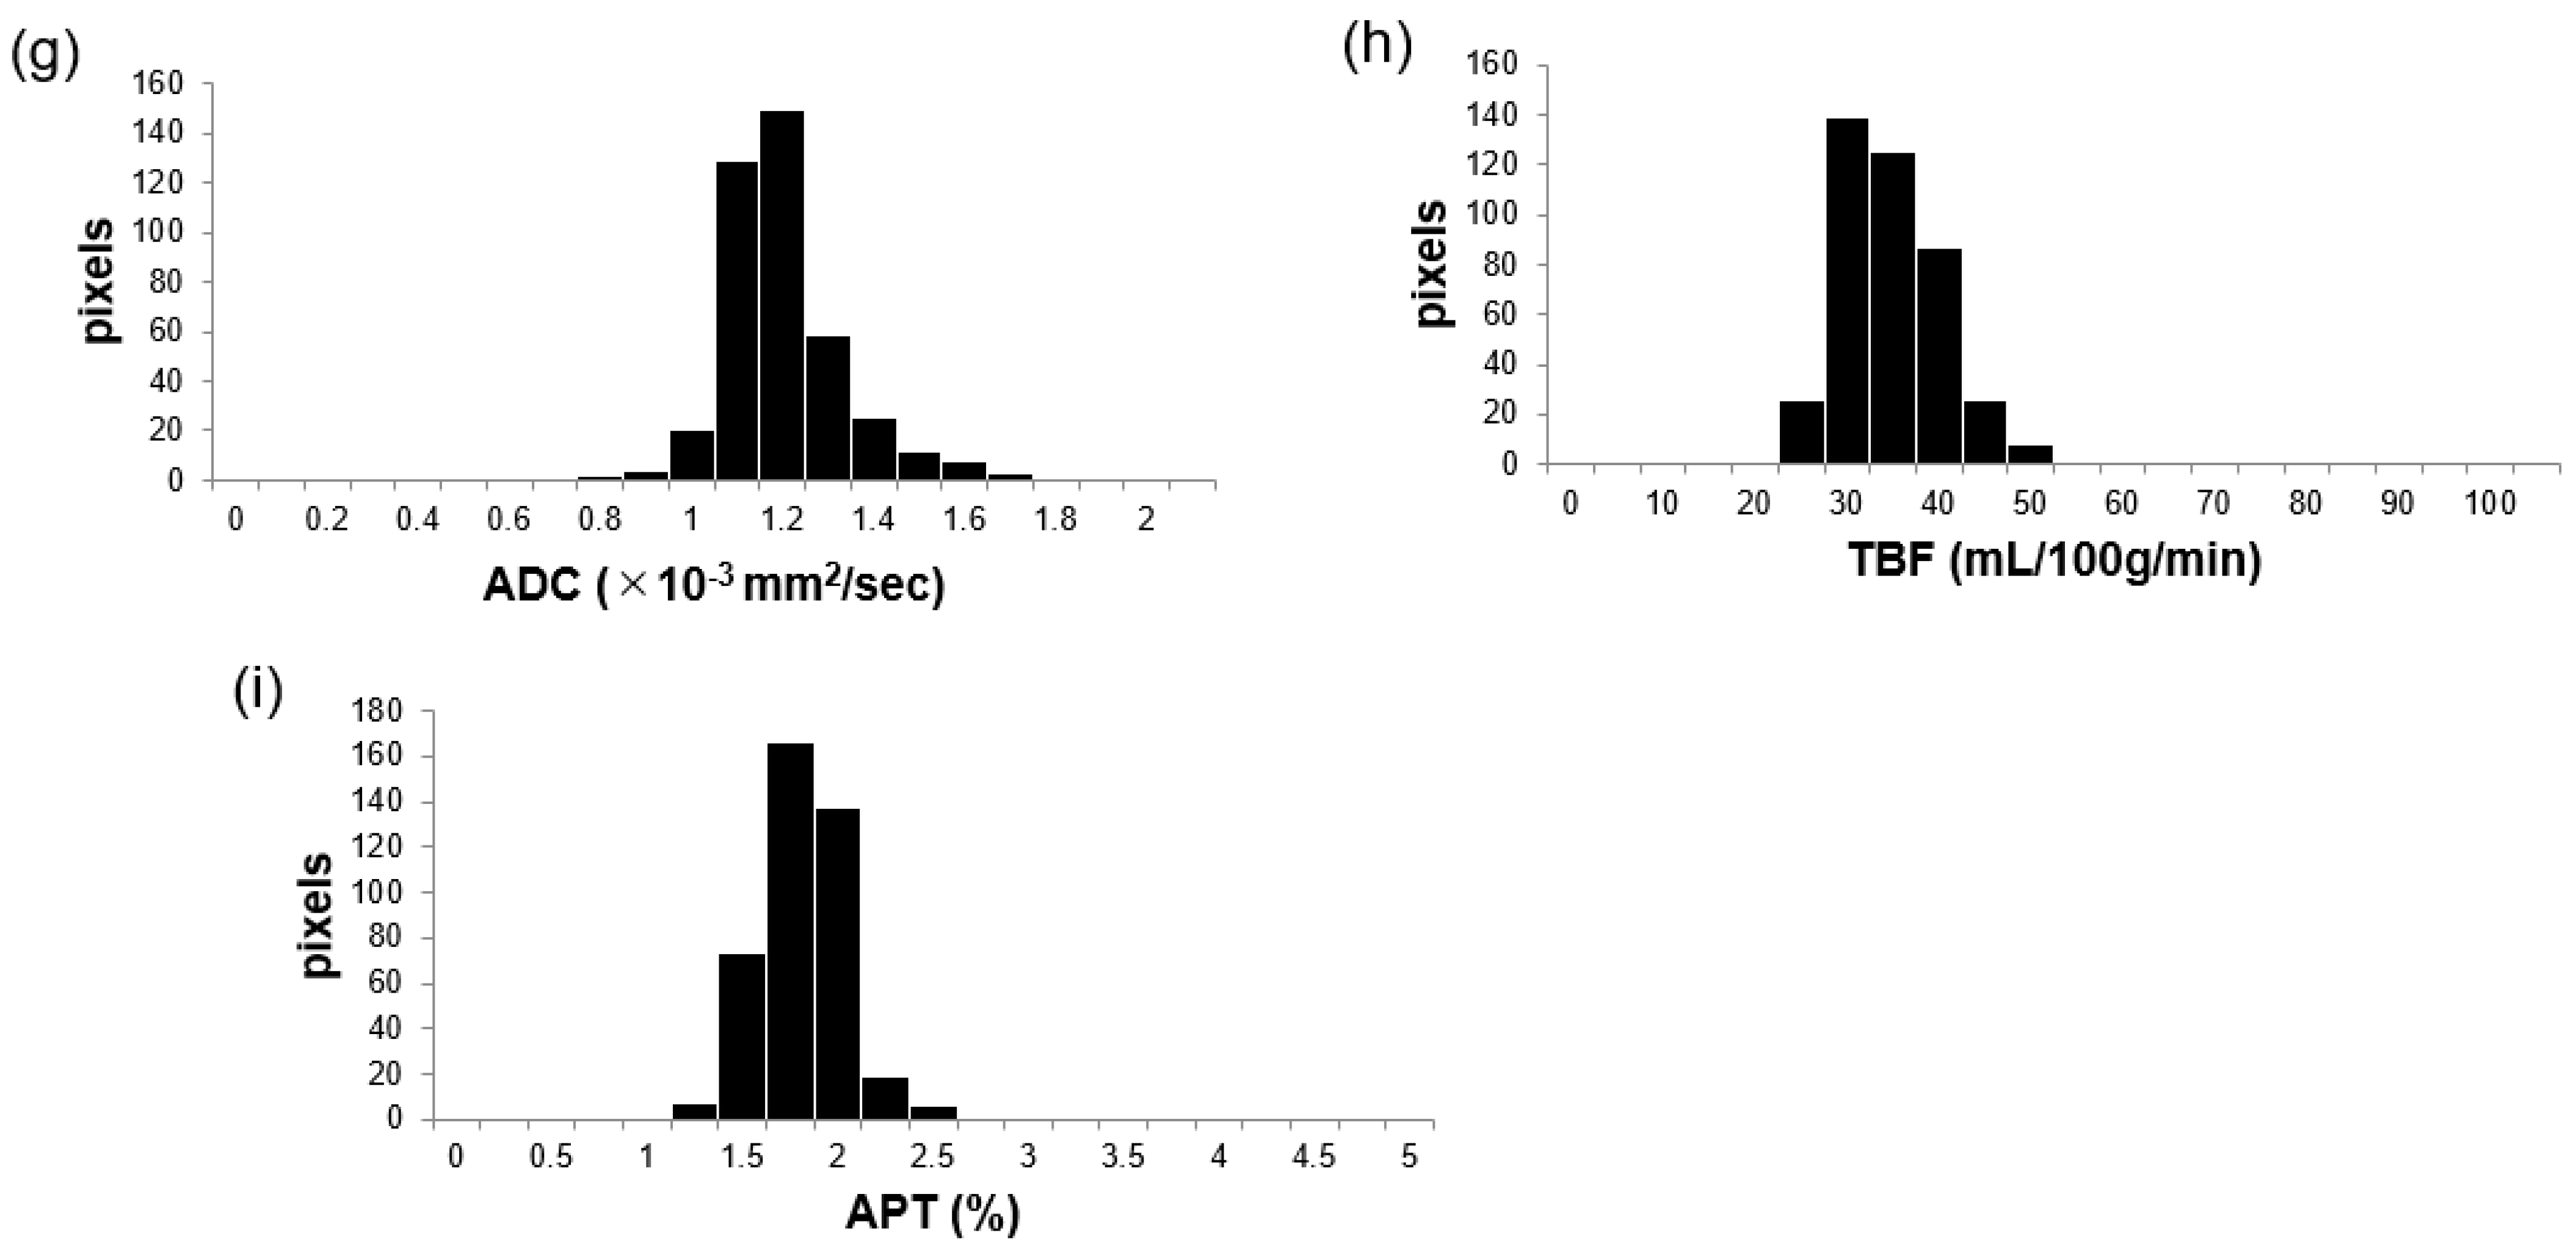

2.3. Image Analysis

3.3. Comparisons of APT, TBF, and ADC Parameters between MTs and BTs

4. Discussion